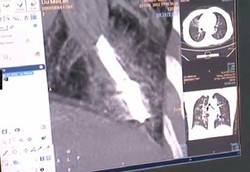

Termometer Terjebak Dalam Paru-paru Wanita Selama 44 Tahun

Seorang wanita di China telah hidup dengan termometer yang terjebak di paru-parunya selama 44 tahun. Ajaibnya, si wanita tidak merasakan keluhan apa-apa meski benda asing itu telah lama berada di dalam tubuhnya.